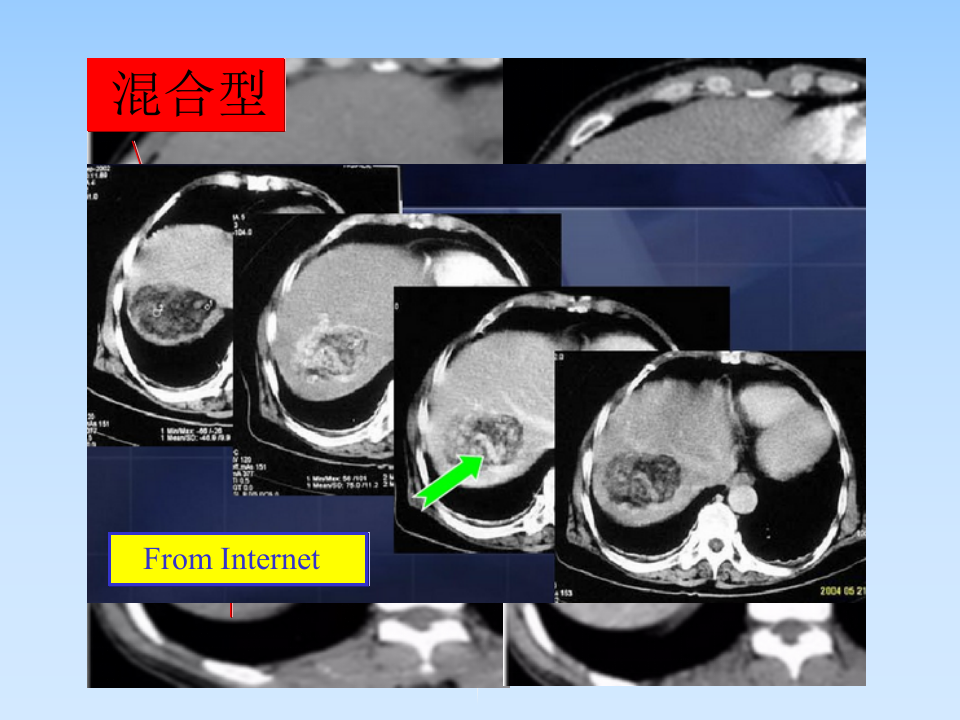

肝AML授课--曾蒙苏.ppt